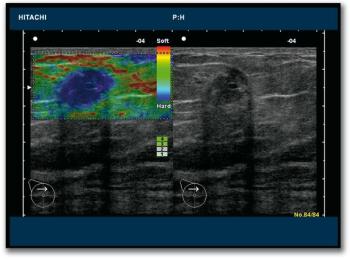

The exhibition booths occupied by vendors of ultrasound systems at ECR 2010 are likely to be very busy places throughout the congress. Difficult economic conditions are causing a dip in global demand for the more capital-intensive modalities like CT and MRI, and hospital managers are keen for their staff to explore the clinical potential of this versatile and cost-effective technology.